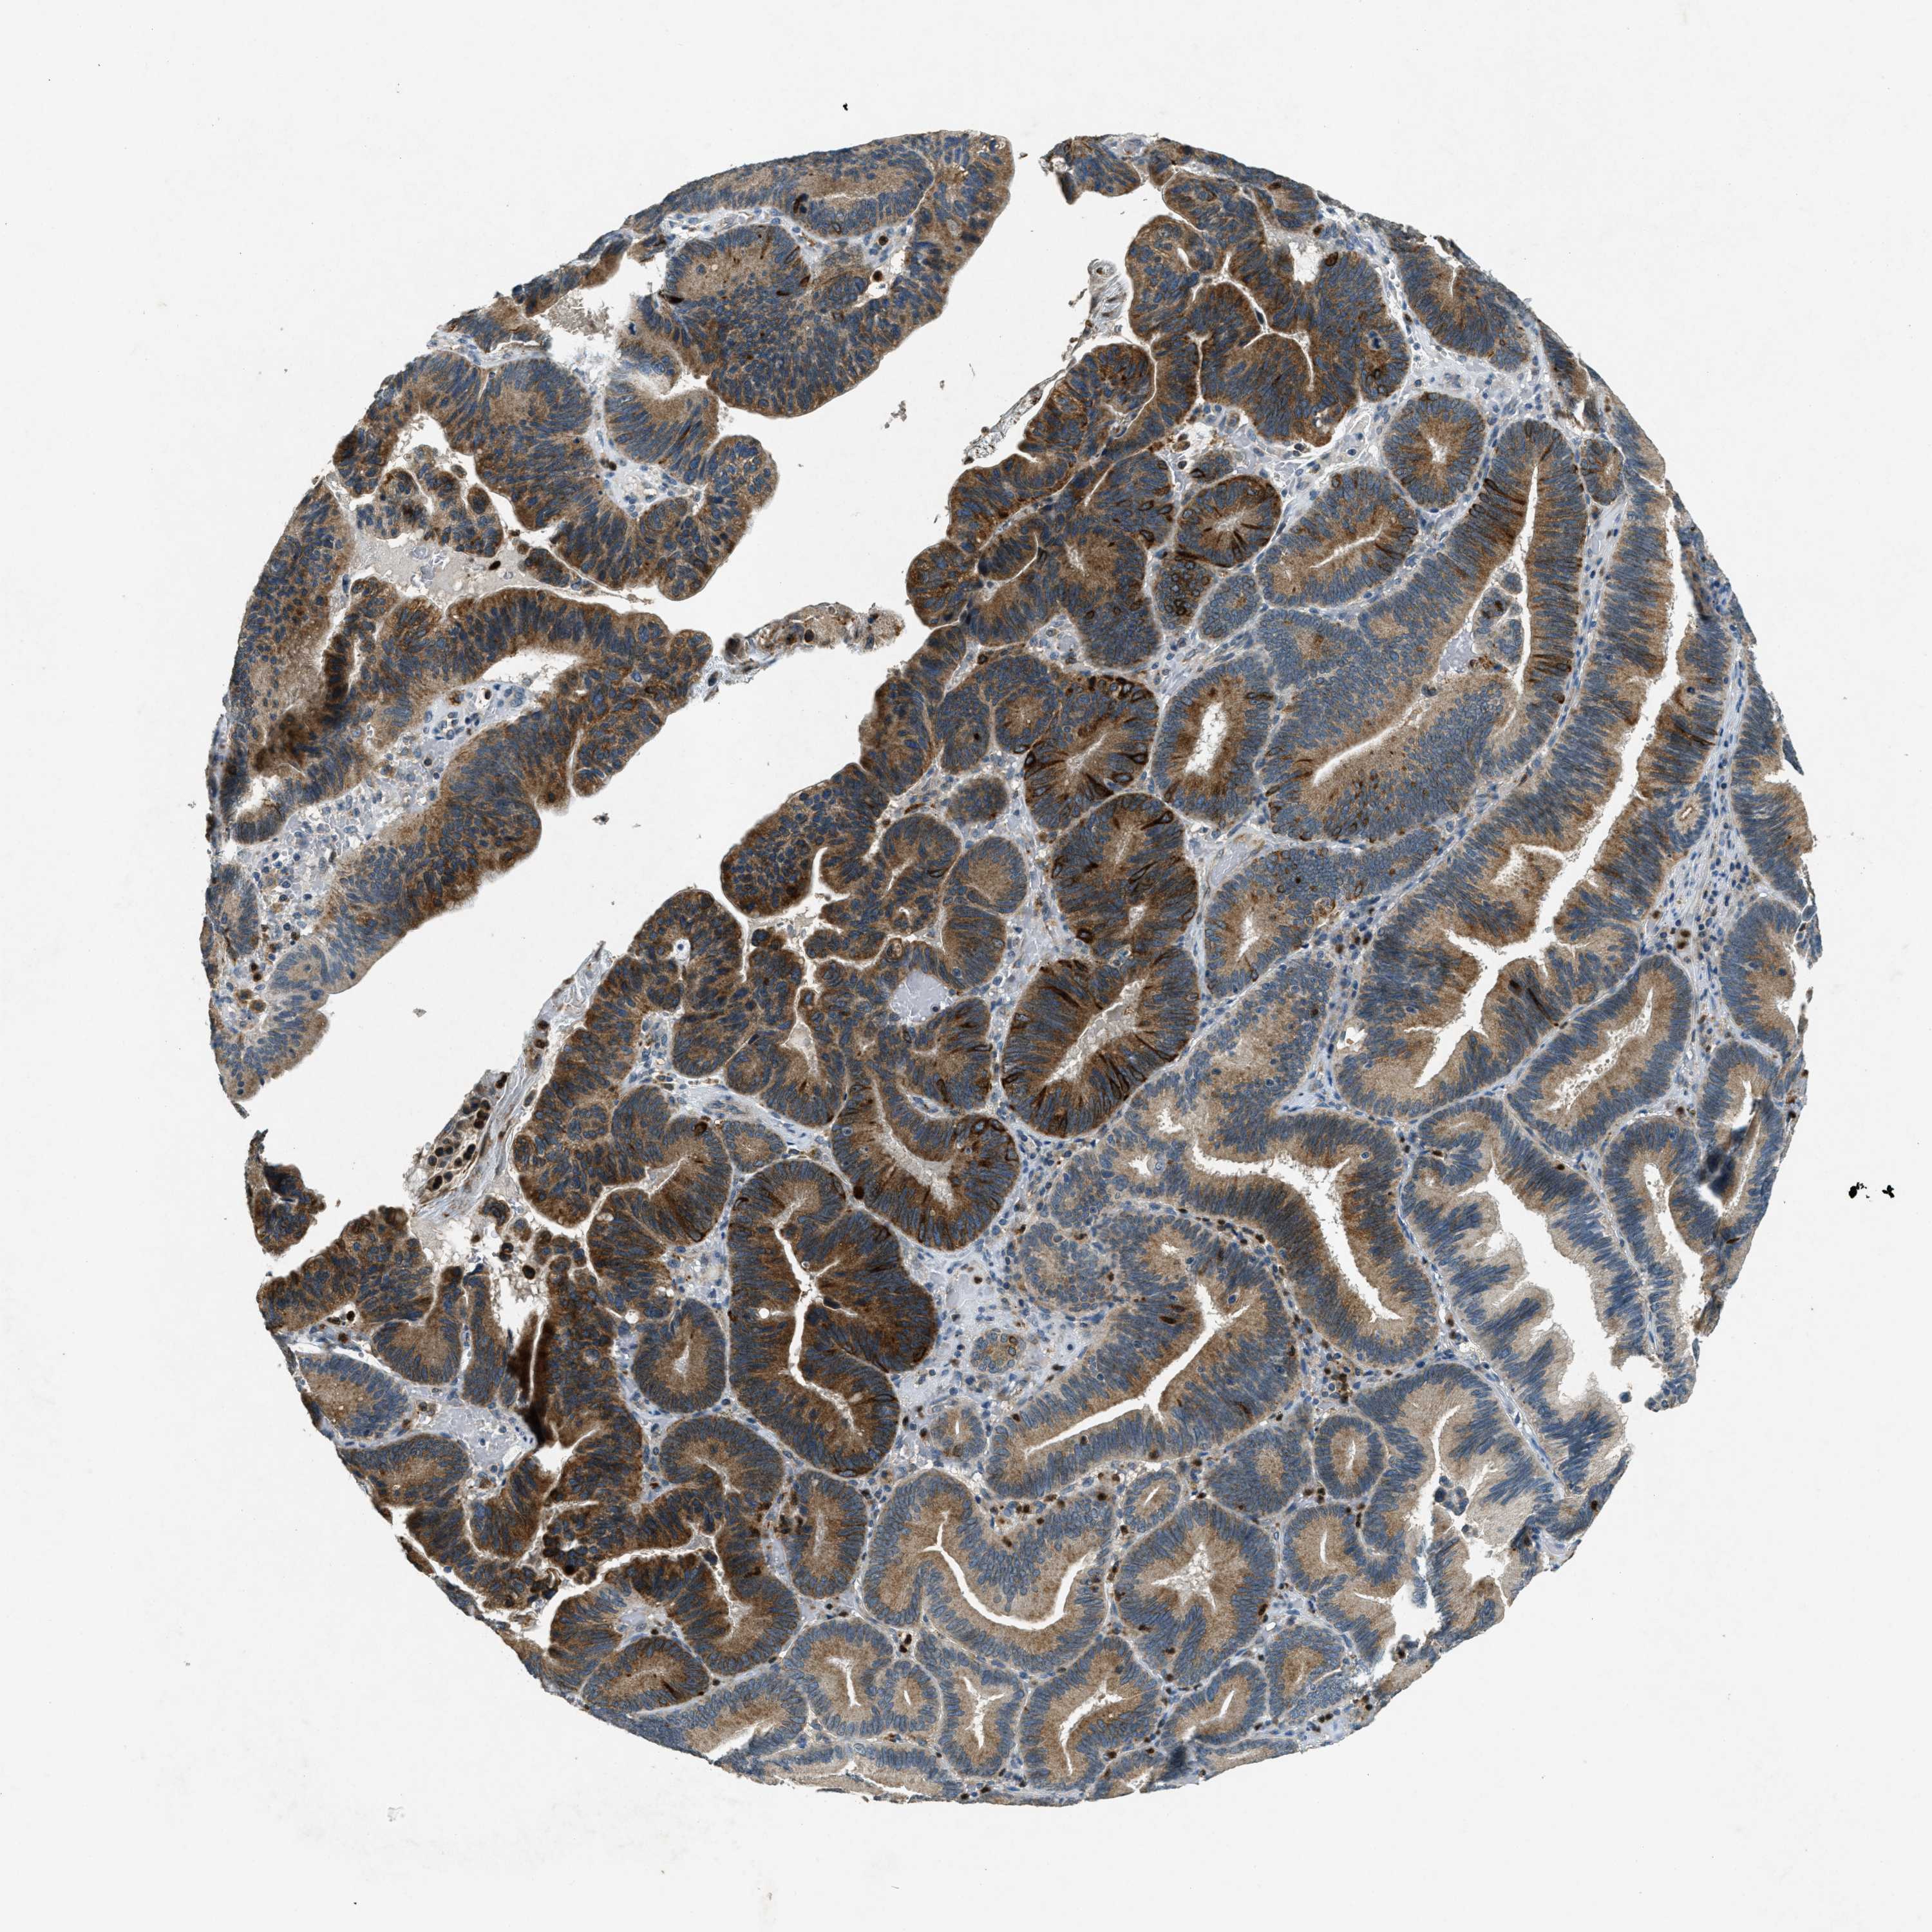

PANCREATIC CANCER - Protein expressioni

A mouse-over function shows sample information and annotation data. Click on an image to view it in a full screen mode. Samples can be filtered based on level of antibody staining by selecting one or several of the following categories: high, medium, low and not detected. The assay and annotation is described here.

Note that samples used for immunohistochemistry by the Human Protein Atlas do not correspond to samples in the TCGA dataset.

Antibody stainingi

Antibody staining in the annotated cell types in the current human tissue is reported as not detected, low, medium, or high, based on conventional immunohistochemistry profiling in selected tissues. This score is based on the combination of the staining intensity and fraction of stained cells.

Each image is clickable and will lead to virtual microscopy that enables deeper exploration of all samples and also displays staining intensity scores, fraction scores and subcellular localization as well as patient and tissue information for each sample.

Antibody CAB018067

Staining

High

Medium

Low

Not detected

Intensity

Strong

Moderate

Weak

Negative

Quantity

>75%

75%-25%

<25%

None

Location

Nuclear

Cytoplasmic/membranous

Cytoplasmic/membranous,nuclear

Adenocarcinoma, NOS

Adenocarcinoma, metastatic, NOS